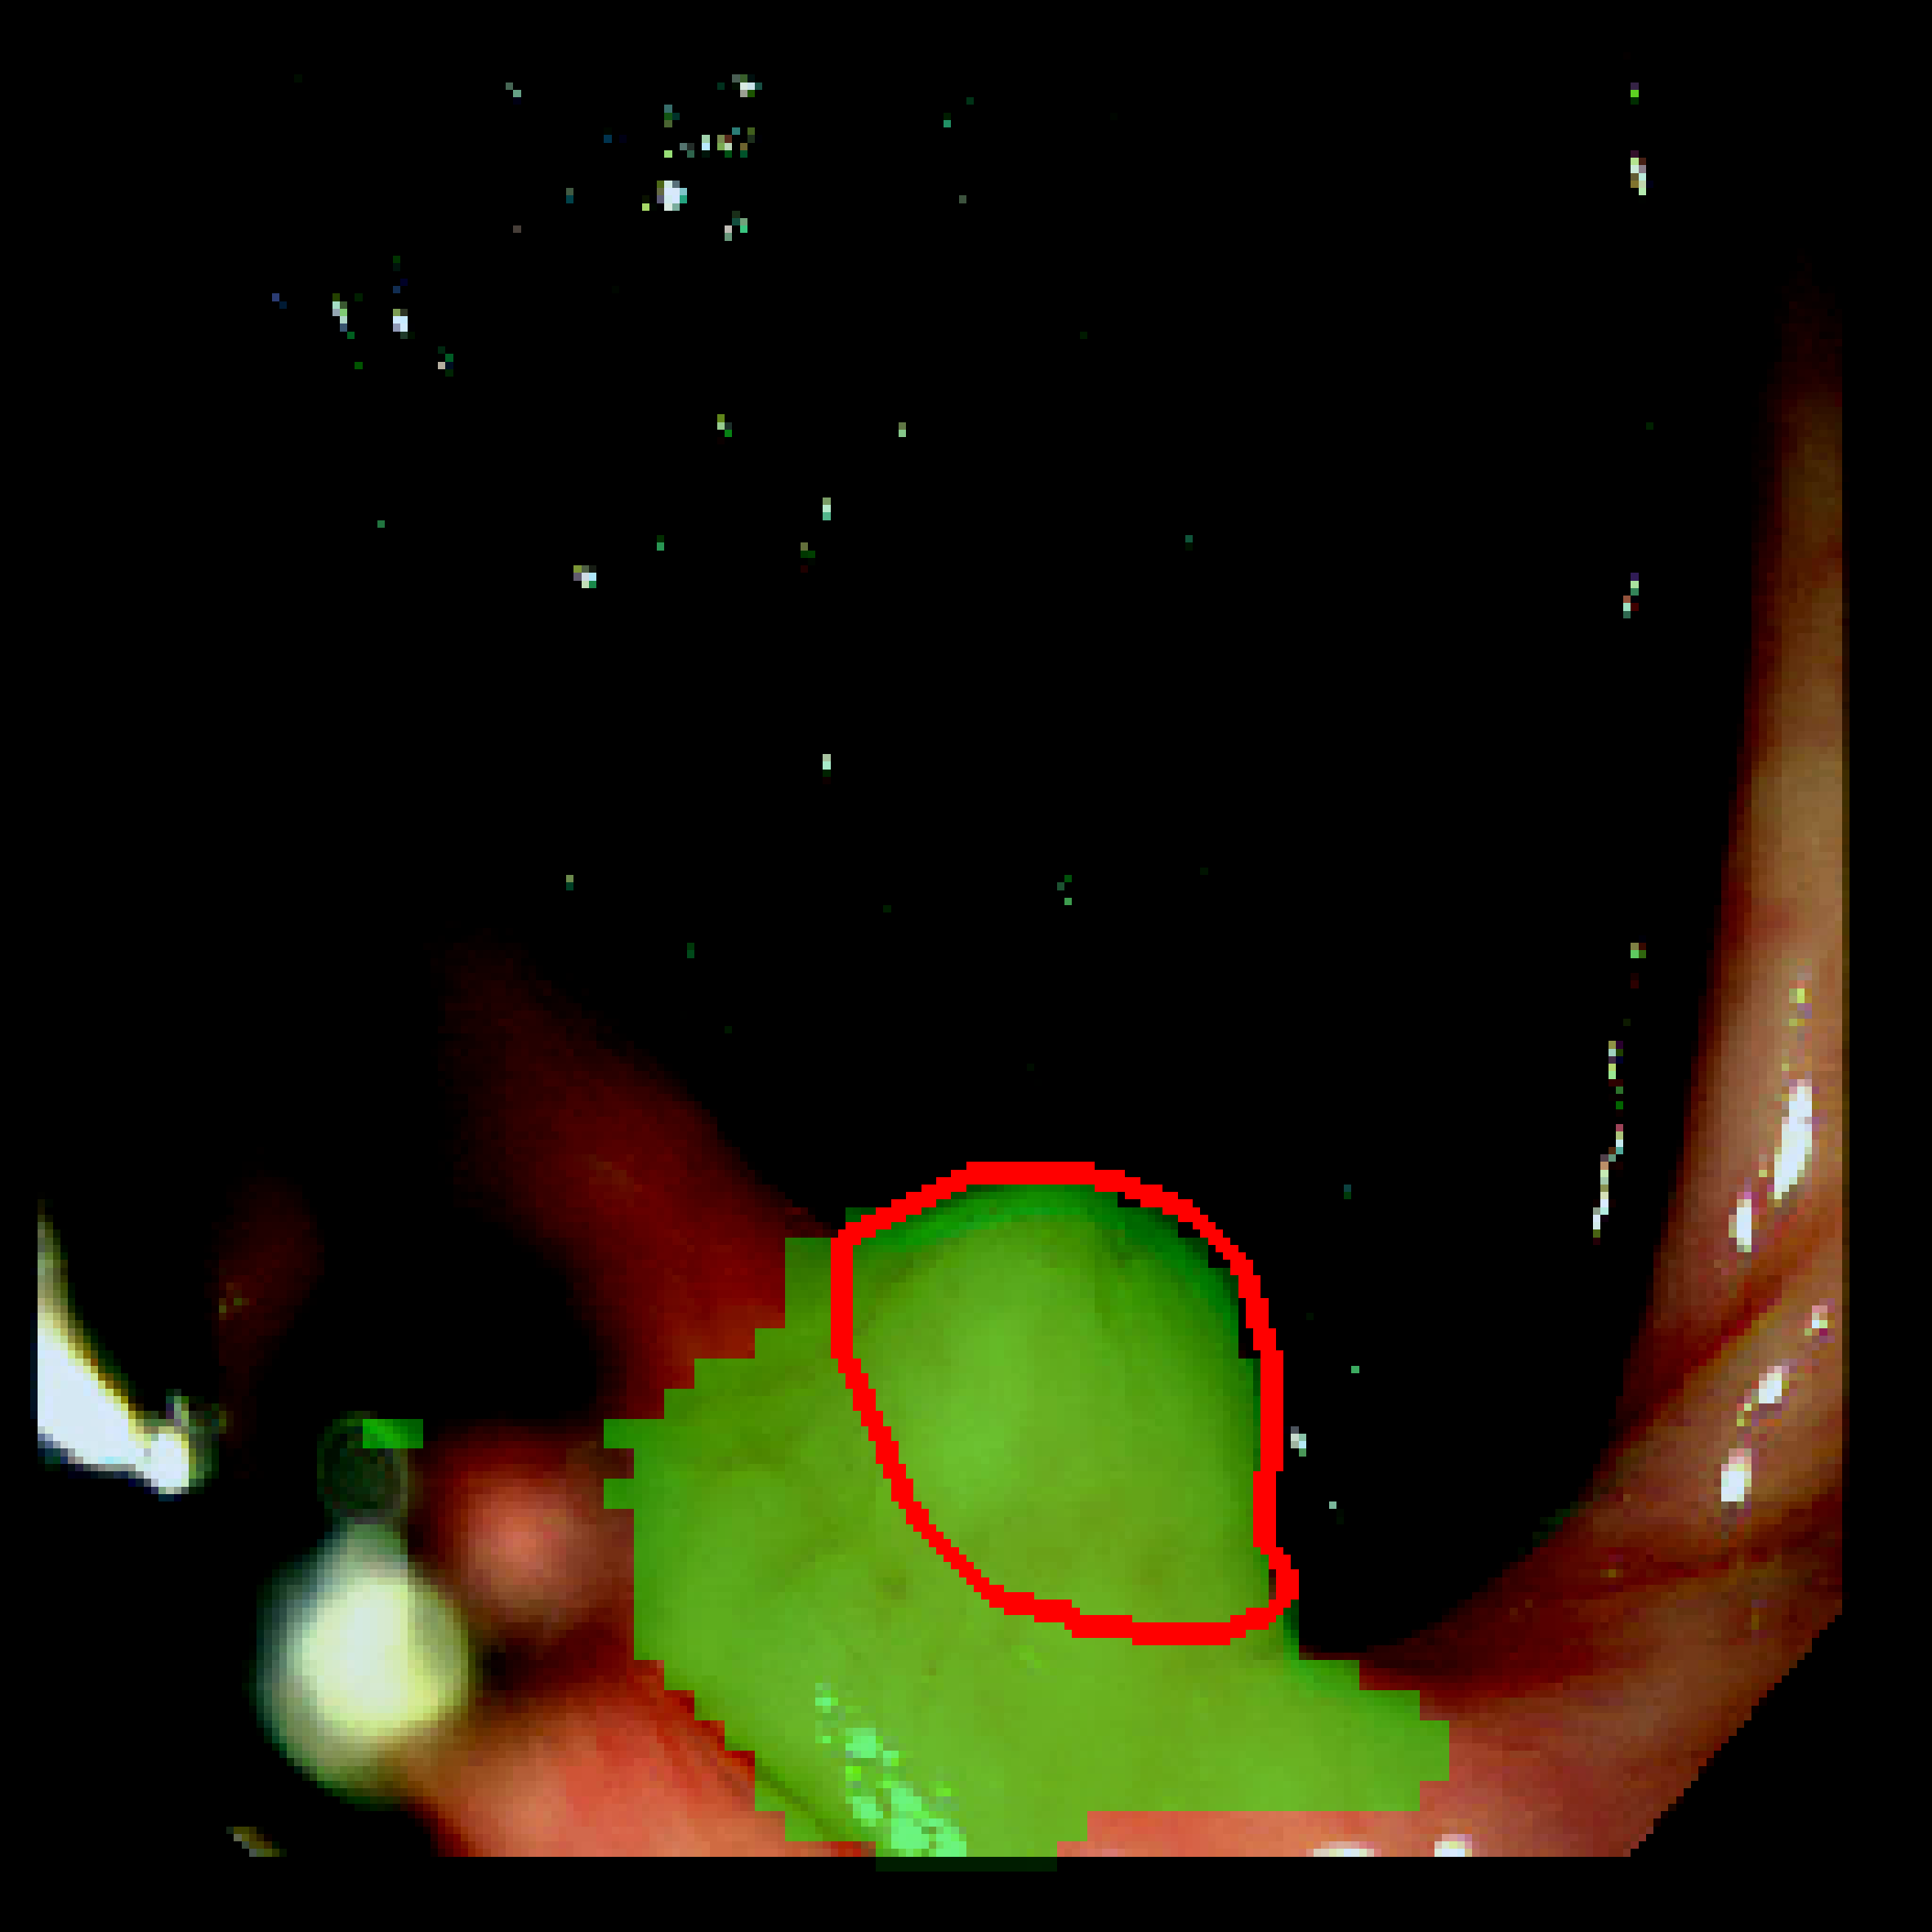

Table 3: Qualitative results of different methods, \Circle and \CIRCLE denote groundtruth and predicted mask, respectively.

SAM MedSAM SAM-Med2D CPC-SAM KnowSAM Ours

5% Promise [Uncaptioned image] [Uncaptioned image] [Uncaptioned image] [Uncaptioned image] [Uncaptioned image] [Uncaptioned image]

10% Promise [Uncaptioned image] [Uncaptioned image] [Uncaptioned image] [Uncaptioned image] [Uncaptioned image] [Uncaptioned image]

5% Colon [Uncaptioned image] [Uncaptioned image] [Uncaptioned image] [Uncaptioned image] [Uncaptioned image] [Uncaptioned image]

10% Colon [Uncaptioned image] [Uncaptioned image] [Uncaptioned image] [Uncaptioned image] [Uncaptioned image] [Uncaptioned image]

For the qualitative results shown in Tab. 3, our method consistently produces more accurate and compact segmentation results for most cases in the PROMISE12 and COLON datasets, effectively capturing the prostate and polyp boundaries while suppressing background noise. In contrast, other approaches tend to over-segment the target regions, leading to the inclusion of irrelevant surrounding tissues. These results visually demonstrate the robustness of our method in handling diverse anatomical variations.